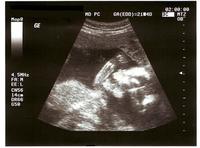

¿Estás embarazada o buscas un bebé? Aprende cómo prevenir los defectos de nacimiento

EmbarazoEn próximo mes de enero es el de la prevención de defectos congénitos y aunque no es posible prevenir todos los defectos de nacimiento, muchos sí pueden ser prevenidos y es posible reducir la probabilidad de que los niños nazcan con esos...